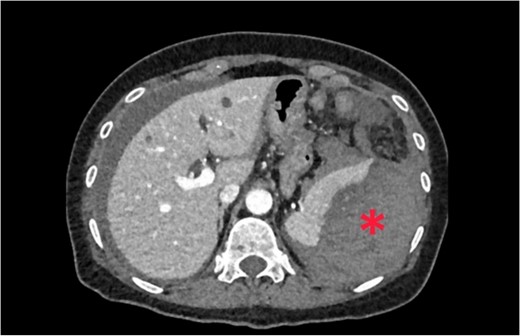

Non-contrast abdominal computed tomography (CT) revealed hemoperitoneum: moderate ascites with organized clot on the surface of greater omentum (Fig. 1)

Computed tomography image on admission: moderate ascites with organized clot.